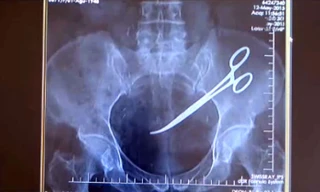

TPO - Các bác sĩ Bệnh viện Đa khoa Trung ương Cần Thơ vừa phẫu thuật lấy thành công chiếc kéo dài 24cm đâm xuyên cổ một nam bệnh nhân 44 tuổi quê Sóc Trăng.

TPO - Bà Hanim Ozgul, 67 tuổi người Thổ Nhĩ Kỳ tá hoả khi phát hiện có một chiếc kéo phẫu thuật nằm trong ổ bụng của mình từ sau ca phẫu thuật điều trị ung thư cách đây 5 năm.